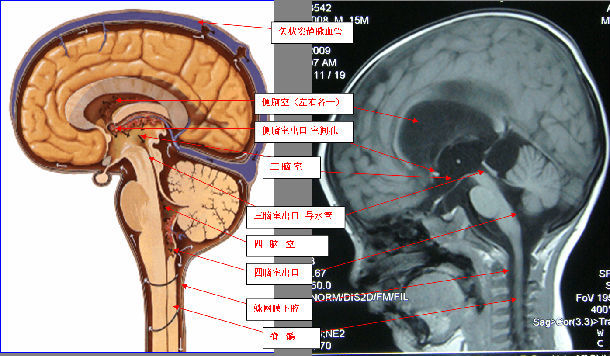

颅腔三分隔&脑脊液循环示意图

脑积水的诊断与治疗